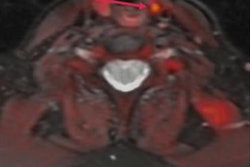

FCH-PET image of an ectopic mediastinal parathyroid adenoma (arrows) on (A) sagittal and (B) axial view fused with simultaneous MRI. This patient had previously undergone a bilateral neck exploration, which had failed to localize a left lower gland. Ultrasound, sestamibi, and 4D CT were all negative. After FCH-PET localization, a robot-assisted left thoracoscopic approach was employed to resect the gland from the aortopulmonary window. Follow-up blood work 8 months after surgery confirmed normalization of calcium. Image courtesy of Surgery.Graves and colleagues found that F-18 FCH-PET localized at least one cancer lesion in 93% of patients overall and in 91% of patients with previously negative imaging, leading to a change in preoperative strategy in 60% of patients. Of 76 patients who underwent parathyroidectomy, 58 (77%) had laboratory data at least six months afterward, with 55 out of 58 of these patients (95%) demonstrating cure.